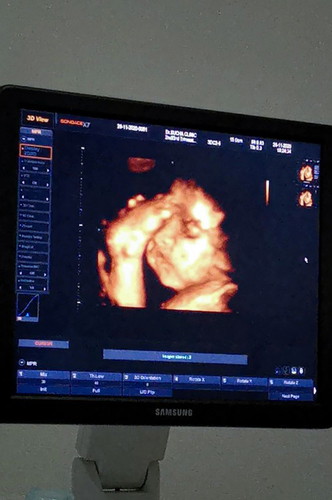

ซาว4D 31W ลุ้นๆว่าจะต้องผ่าหรือป่าวครับ

หมอบอกว่าน้องมีโอกาสกลับหัวน้อยครับ70/30ตอนนี้31สัปดาแล้วครับมีโออาสที่จะต้องผ่าส่วนตัวพ่อก้อยากผ่าเพราะตรงกับวันเกิดตัวเองพอดี ส่วนคุณแม่ก้อยากคลอดเองต้องรอลุ้นครับ.. พึ่งจะซาว4Dชัดๆก้งวดนี้แหละครับ เห็นรูปแรกก้งงเรย🥺🥰น้องเอาเท้ากายหน้าผากเรยครับสงสัยจะเครียดครับ เป็นกำลังใจให้น้องมารีนด้วยนะครับ😍😚